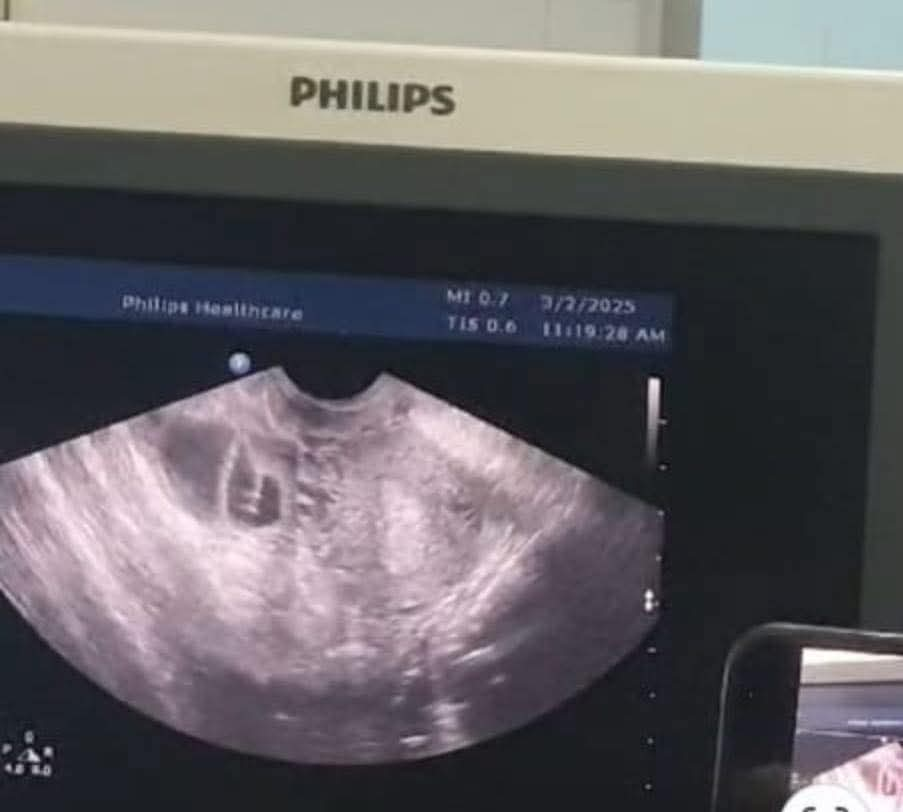

وأكد رئيس اختصاص العقم أن العملية نُفذت بدقة عالية وتحت توجيه الموجات فوق الصوتية من قبل فريق طبي متعدد التخصصات من أطباء العقم، الأشعة، والجهاز الهضمي، وأن هذه الخطوة تمثل نقلة نوعية في طب الإخصاب والعقم، وتعزز من مكانة الخدمات الطبية الملكية كمركز رائد في تقديم الرعاية الصحية التخصصية بأعلى المعايير الأخلاقية والطبية على مستوى الأردن والمنطقة.